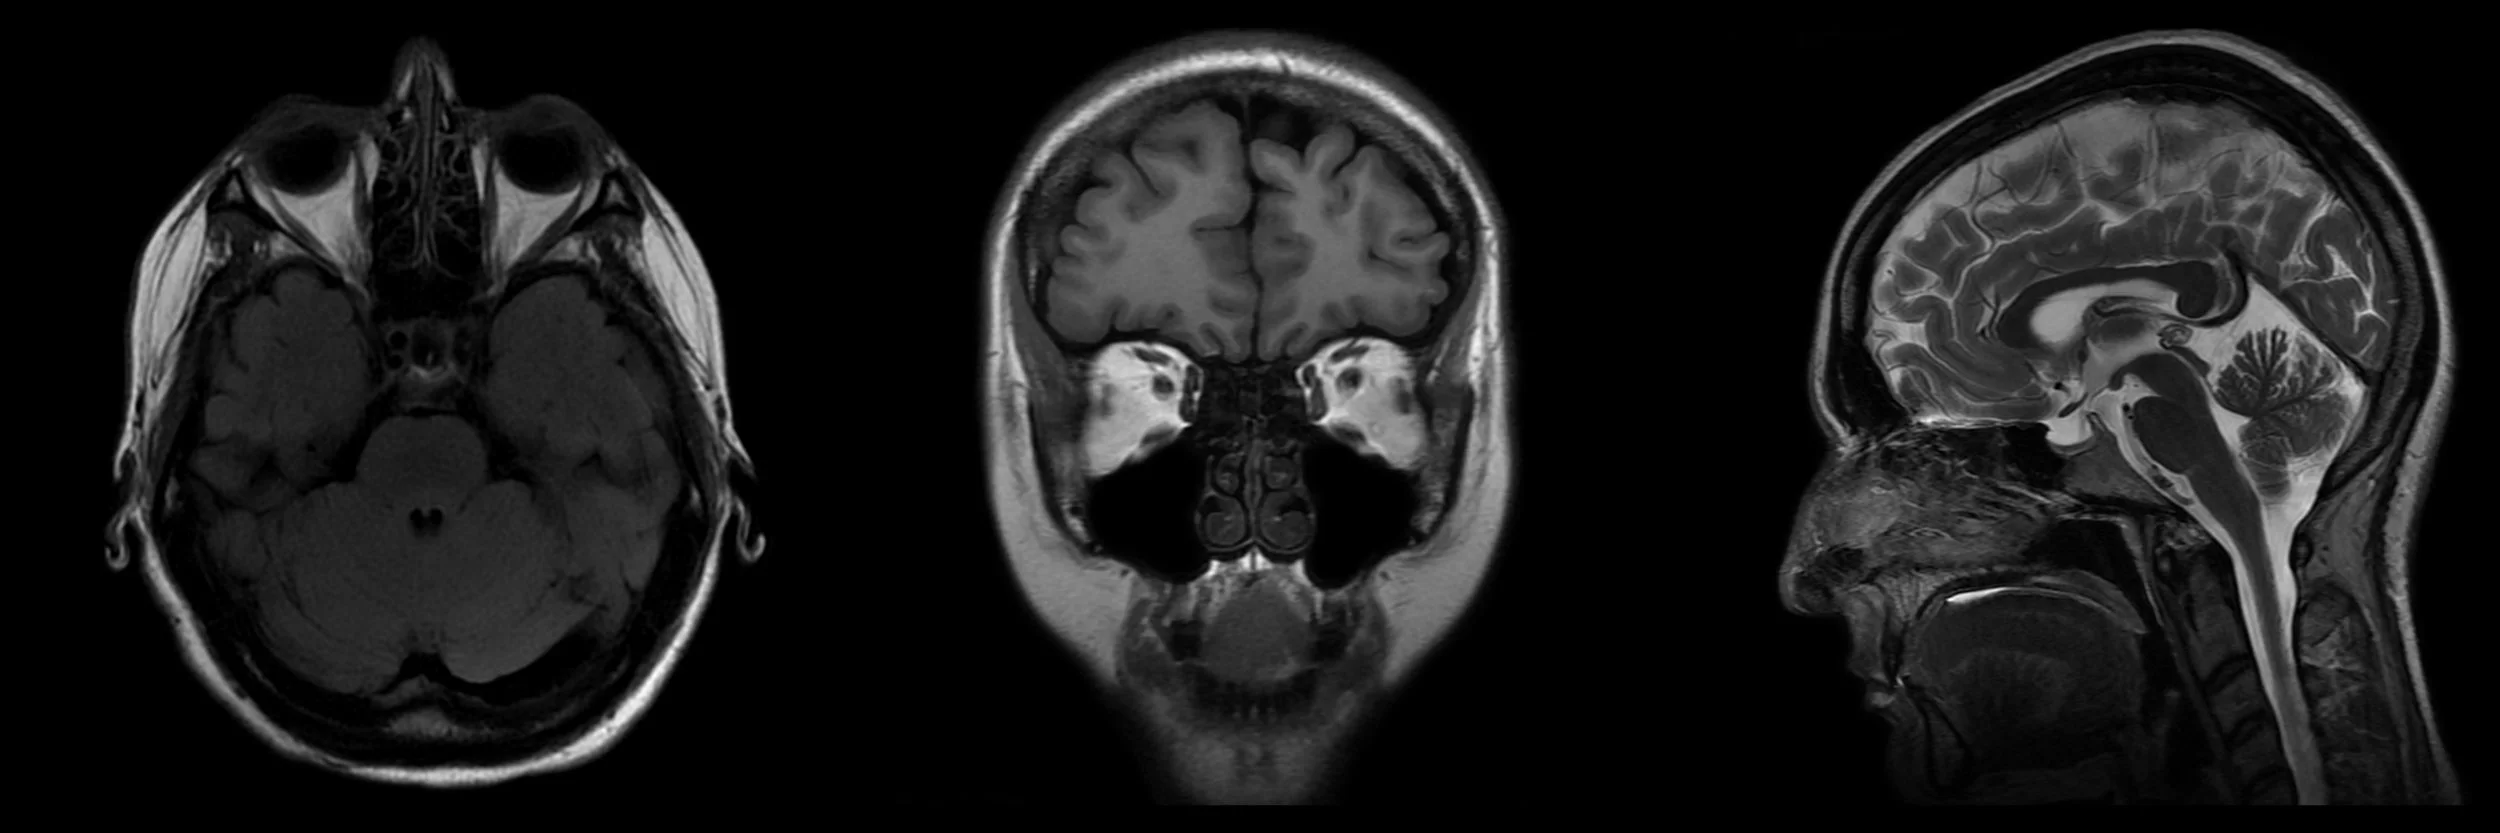

Neuroimaging standards for research into small vessel disease and its contribution to ageing and neurodegeneration

An international working group from the Centres of Excellence in Neurodegeneration completed a structured process to develop definitions and imaging standards for markers and consequences of SVD. Their aim was to achieve the following: first, to provide a common advisory about terms and definitions for features visible on MRI; second, to suggest minimum standards for image acquisition and analysis; third, to agree on standards for scientific reporting of changes related to SVD on neuroimaging; and fourth, to review emerging imaging methods for detection and quantification of preclinical manifestations of SVD. Their findings and recommendations apply to research studies, and can be used in the clinical setting to standardise image interpretation, acquisition, and reporting. This Position Paper summarises the main outcomes of this international effort to provide the STandards for ReportIng Vascular changes on nEuroimaging (STRIVE).